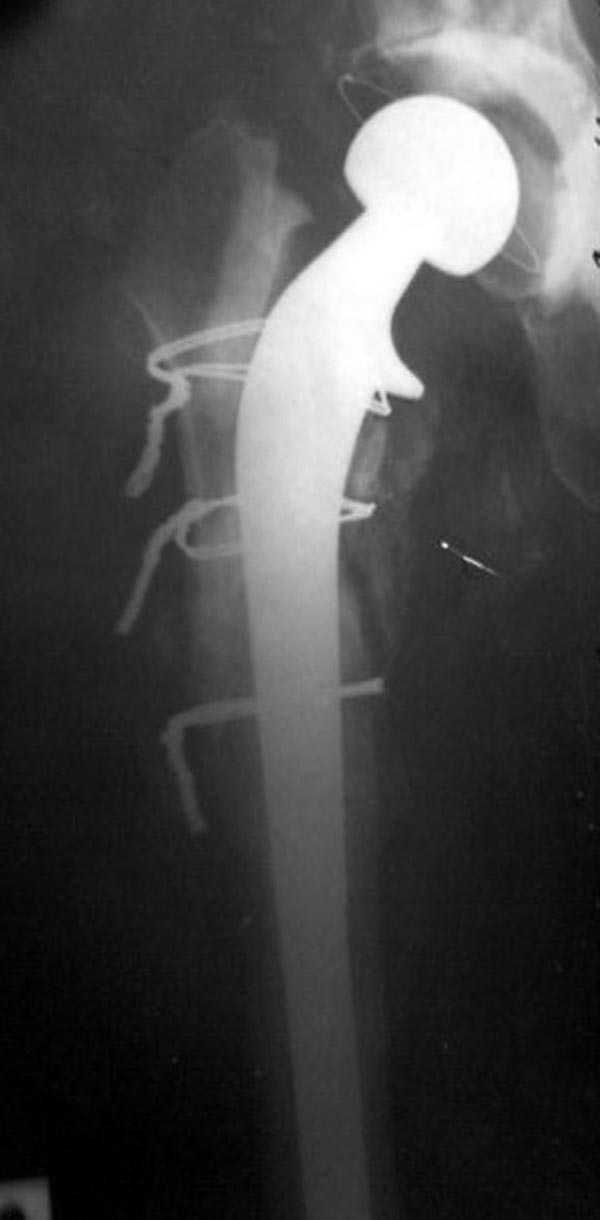

Следующий этап восстановление применением Blade Plate. Универсальный имплант и сегодня является уникальным по механическим характеристикам для восстановления проксимального отдела бедра где имеется сложная биомеханика.

Имеющиеся 130 градусные для вальгуса пластины от

Synthes короткие всего на две дырки, выход, обычная длинная 95 градусная Blade Plate разгибается до 105-110 градусов. Металл трудно поддается деформации, и его не согнуть между тепловой батереей в операционной, надо подготовить заранее после предварительного нагрева в механической мастерской.

Проведя клинок горизонтально в шейку, и соединив с

диафизом бедра создаем небольшой вальгус, тем самым увеличиваем длину конечности. Образовавшийся дефект кости надо заполнить блоком цемента, который предупреждает инфицирования и дает устойчивость конструкции. После затихания процесса можно приступить ко вторичному заполнению аутокостью или можно применить костную массу из того же местного костного регенерата.

Обещанный Synthesом локинг вариант пластины еще до нас не дошел, но блокирующая на пластине шайба поможет созданию локинг концепт.